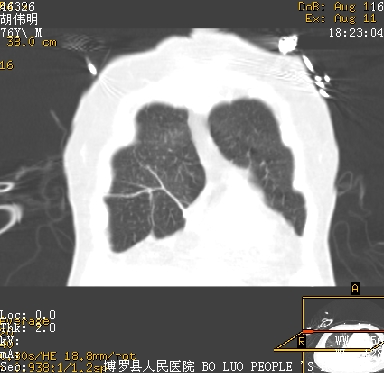

icu病人,几天都没明确诊断。m,76y,咳嗽、咳痰1周,伴气促,右胸痛入院,pe:t38.3c p135 r25 bp135/85。双肺可闻及大量湿罗音,心、腹未见明显异常。诊断:1心衰?2肺部感染?3冠心病?

9号平片

11号ct

双肺感染性病变,下叶膨胀不全,胸水,左室大。

1)两肺感染性病变(右肺下叶肺脓肿可能)。2)双侧胸腔积液,以右侧为甚。

ards,肺感染性病变,右下叶实变,双侧胸腔积液,右侧为著,叶间胸膜积液,右上肺陈旧性tb纤维灶,左室大。